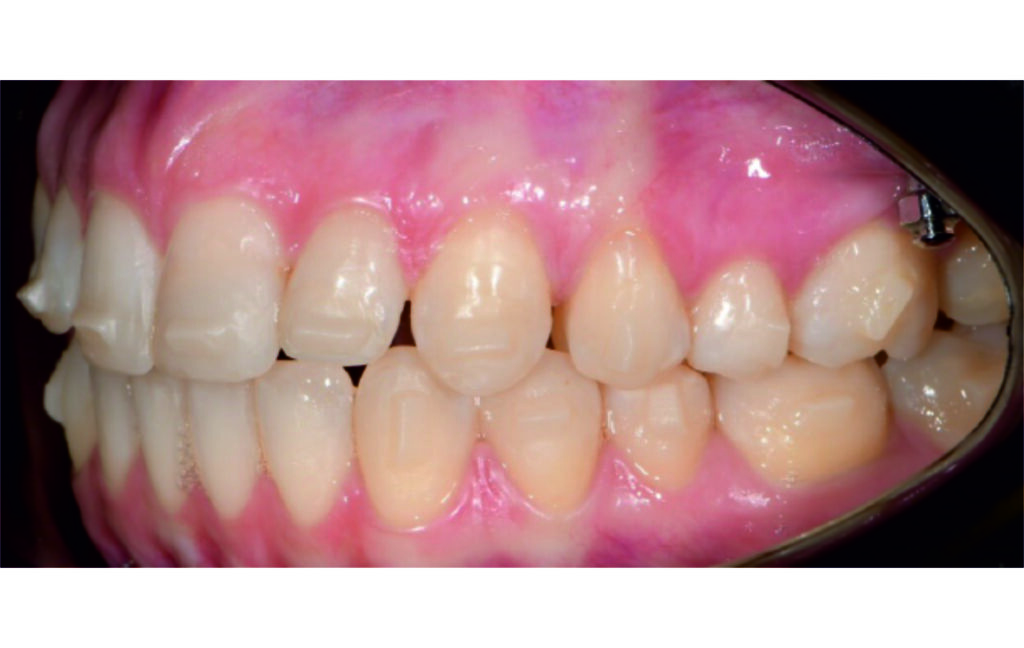

Angle Class II 2mm on the right, Angle Class II 2mm on the left, light mandibular asymmetry to the right, lower central line 1mm to the right, upper central line 1,5mm to the left, 1mm overjet and overbite. Sagittal asymmetry of upper dental arch. Light crowding upper and lower frontal segments, severe attrition of posterior teeth, night bruxism. Normal sagittal position of both jaws, high angle case, steep mandibular ramus,excessive lower facial height, open bite tendency.

The case initially presented as a moderate Class II on the right and a Class II tendency on the left, with tapered dental arches and an anterior open bite extending to tooth 26 in segment II.

In segment I, the open bite reached up to the first premolar.

A 1.5 mm deviation of the upper dental midline to the patient’s left was noted, along with a slight mandibular midline shift to the right, likely due to asymmetrical mandibular growth observed in the facial structure. Severe mesial rotations of teeth 16 and 26 were evident in the initial records. As derotation of 16, 26, 17, and 27 progressed up to aligner 16, the premolars in segments I and II moved distally, resulting in a bilateral Class I relationship, as intended in the initial treatment plan.